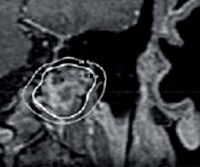

• Инструментальные исследования. Для определения характера поражения, размеров и расположения патологического образования используют рентгенографию, КТ височной кости. Магнитно-резонансная томография позволяет определить степень повреждения вен и артерий головы. Ангиография используется непосредственно перед операцией и определяет источники кровоснабжения клубочков.